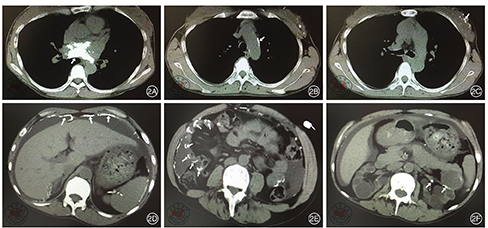

患者,女性,27岁。2010年3月26日因贫血4个月,颜面、下肢浮肿1周到南京医科大学附属无锡第二人民医院就诊。为求进一步诊治入院。实验室检查:血红蛋白(hemoglobin,Hb)57 g/L,血肌酐1657.0 umol/L,血压160/120 mmHg,尿常规蛋白4+,免疫功能正常,抗核抗体谱阴性。超声提示双肾萎缩。考虑慢性肾小球肾炎引起肾功能衰竭。入院诊断为:慢性肾衰竭尿毒症期;慢性肾小球肾炎;肾性贫血;肾性高血压。患者血肌酐高达1657.0 umol/L,入院后立即行右颈内静脉深静脉置管血液透析,硝苯地平控释片和美托洛尔控制血压,叶酸片、速力菲、促红素改善贫血,还原型谷胱甘肽和阿魏酸钠保肾治疗。甲状旁腺激素(parathyroid hormone,PTH)350 pg/ml,α-骨化醇纠正甲状旁腺功能亢进。血液透析后血肌酐降至775 umol/L,继续一周3次血液透析。出院复查Hb 87 g/L,血肌酐215.0 umol/L,血压120/86 mmHg。2010年5月1日因颈静脉置管感染,改行腹膜透析治疗,一天4次。2011年1月2日患者腹膜透析时不慎被他人扯拉腹透管,致皮下卡夫外漏,出现继发性腹膜炎。为避免再次发生腹膜炎,左前臂动静脉内瘘手术进行血液透析治疗。术后内瘘闭塞,继续维持腹膜透析。2015年4月9日腹膜透析管更换术。至此以后一直维持性腹膜透析治疗。期间出现两次腹膜炎,均经抗感染治疗后好转。2018年11月22日因胸闷入院。患者慢性肾病面容,贫血貌。食欲不佳,偶有恶心、呕吐、头晕。目前透析方案为2.5%透析液(每1000 ml含葡萄糖2.5 g、氯化钠5.67 g、氯化钙0.257 g、氯化镁0.152 g、乳酸钠5 g)2000 ml,每天4袋,夜间留腹。24 h超滤700 ml。腹膜平衡试验:总尿素清除指数(KT/V)1.995/周,总肌酐清除率(total creatinine clearance,Ccr)51.966 L/周。实验室检查:血甲状旁腺激素(parathyroid hormone,PTH)1279.00 pg/ml,血钙2.39 mmol/L,血磷2.47 mmol/L,钙磷乘积73.27 mg/dl。心电图检查:正常窦性心律。甲状腺超声显示:甲状腺左右叶后方探及大小分别为0.8 cm×1.3 cm、0.7 cm×1.5 cm低回声结节,边界清,内回声欠均匀,其内可见条状血流信号。考虑甲状旁腺功能亢进,甲状旁腺腺瘤。2018年11月26日经胸超声心动图显示(图1):左心室射血分数为62%,胸骨长轴切面测室间隔舒张末期厚度为1.2 cm,左室后壁舒张末期厚度为1.2 cm,左室舒张末期内径为4.4 cm,左室质量指数(LVMI)141 g/m2,考虑左室壁向心性重构。心尖四腔切面探查二尖瓣血流频谱E/A=0.8 ,二尖瓣环组织多普勒频谱测二尖瓣环外侧e'为7.51 cm/s,二尖瓣环室间隔测e'为6.27 cm/s,E/e'= 12。左心房前后径43 cm。考虑患者舒张功能障碍II级。胸骨旁长轴及心尖四腔心切面见左房内数个不规则增强回声团,不随血流运动。主动脉瓣环及二尖后叶瓣环回声增强,瓣叶活动正常。为明确诊断2018年11月28日行胸、腹部CT平扫检查(图2):左房内团块状钙化,占据左房大部,与超声心动图检查结果一致。患者主动脉弓、双侧乳腺、腹膜、肠系膜、肾动脉同时存在多发性钙化。2019年2月18日在全麻下行甲状腺旁腺次全切除。病理检查示:甲状旁腺腺瘤样增生。术后第2 d复查PTH 23.77 pg/ml,血钙1.32 mmol/L,血磷1.26 mmol/L。患者PTH、血磷恢复正常,存在低钙血症,加强补钙。2019年10月21日患者为行腹膜平衡试验及进一步诊治,收住我院。复查血钙,血磷,PTH均在正常范围。复查超声心动图及胸、腹部CT平扫检查,钙化较2018年11月检查结果无明显改变。